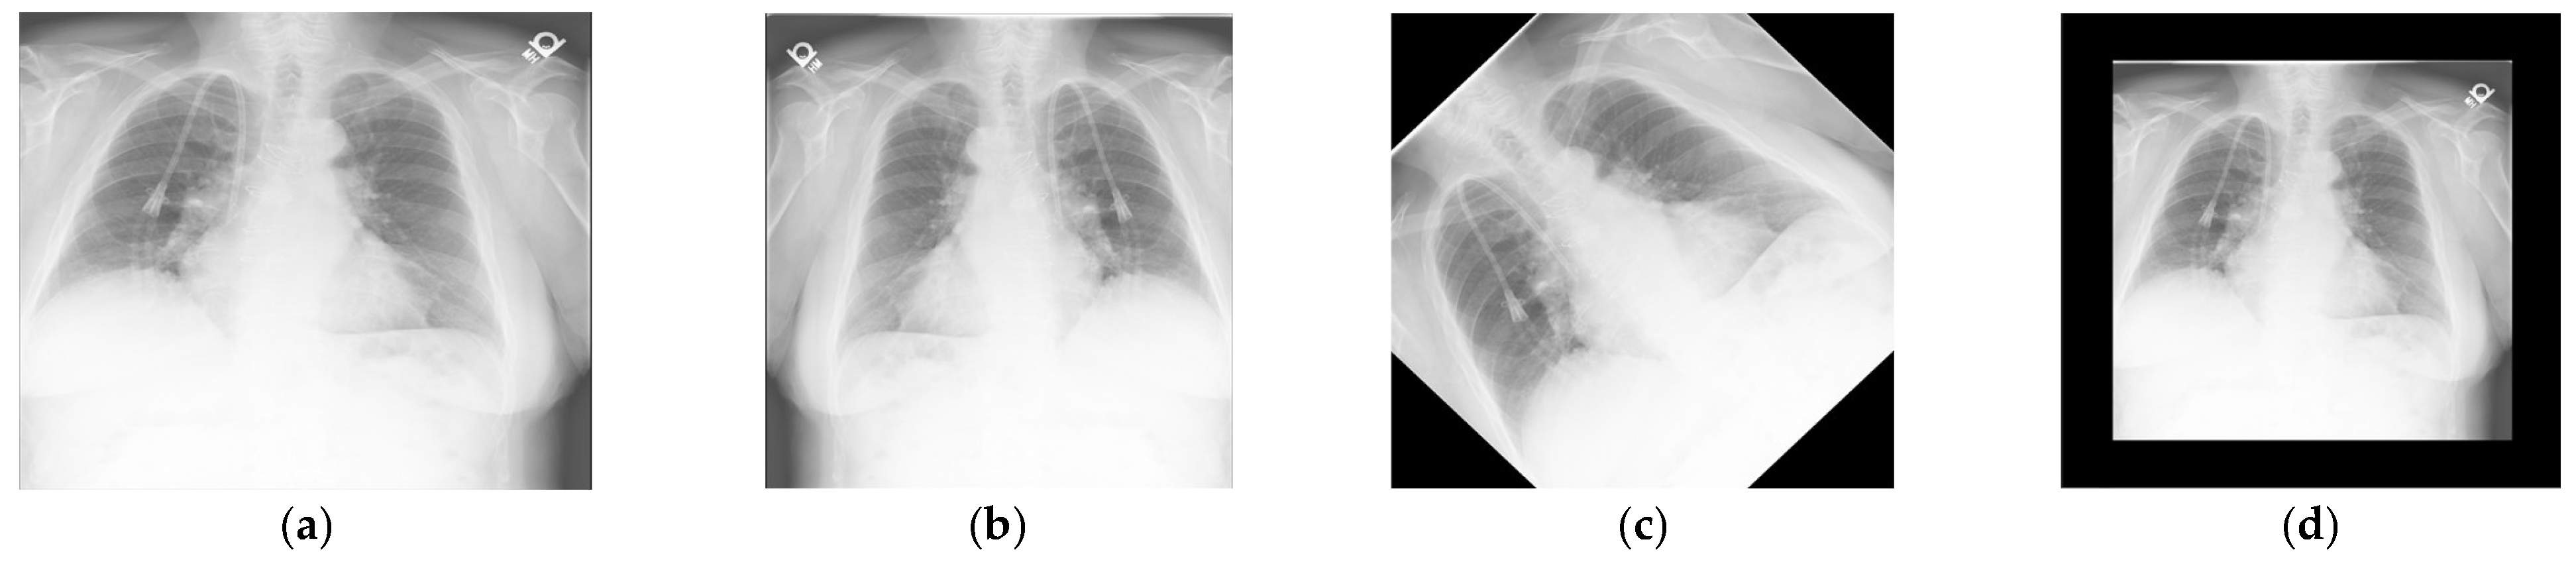

This study utilized the Indiana University Chest X-ray Collection [27], consisting of 7466 chest X-ray images, each accompanied by its corresponding diagnostic report. The diagnostic reports include seven sections, but this research only utilized three for report generation: Indication, Findings, and Impression. Other sections are privacy-related and not used. When training with the IU Dataset, the distribution between the training and test sets was 80% for training and 20% for testing. As shown in Figure 5, data augmentations such as horizontal flipping, rotation, and resizing were applied to the images to prevent overfitting. Despite these augmentations, the diagnostic reports of the augmented images remained identical to those of the original images. In the end, the total dataset comprised 29,632 images.

Figure 5. Images for data augmentation. (a) Original image. (b) Horizontal flipping. (c) Rotation. (d) Resizing.